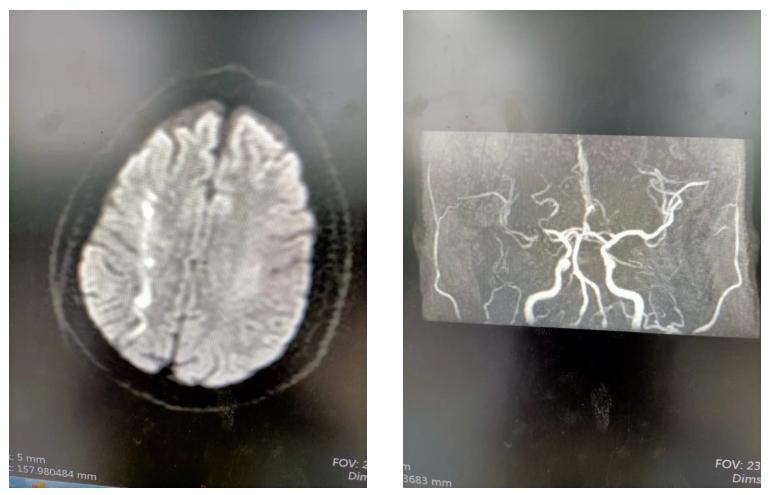

入院时核磁共振显示患者脑部血栓,卒中团队没有放松,术后立即为患者行核磁共振检查,发现右侧大脑中动脉M1段重度狭窄,M1段只剩一条缝隙,患者随时有再次发生大面积脑梗死的风险。神经内科立即向院本部报告患者病情,在与上级医师、患者家属充分沟通病情后,院本部刘福德医生第一时间赶到东院区(阎良区)介入手术室,此时行脑血管造影检查提示,右侧大脑中动脉再次闭塞,预判的风险果然发生了。刘福德医生立即为患者行大脑中动脉取栓手术,并给予球囊扩张+支架植入术,手术过程顺利,血管顺利再通。